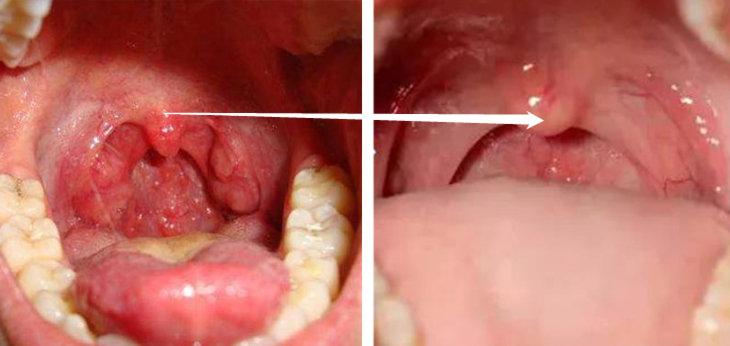

咽炎的常见症状一般是:喉咙有异物感、干痒、有黏痰不易咳出,所以让人不由自主地想咳嗽清嗓子。

频繁这样做,会引起声带和咽部肌肉频繁且剧烈地收缩,牵拉黏膜,造成声带黏膜和咽部黏膜损伤,黏膜下充血。

不仅可能加重炎症反应,还可能导致声带小结。

所以,用上一段时间你会发现:原本受损的咽喉,现在不再有红肿感、吞咽不在有异物感、不再干燥、声音也不再嘶哑了。